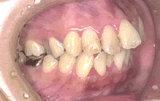

症例2/歯並びがでこぼこしている

【歯科治療前】